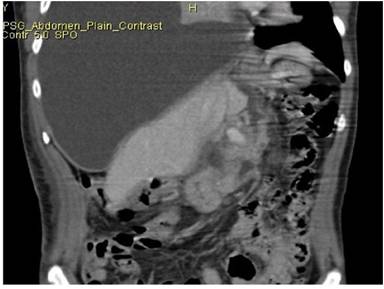

A forty five year old male, case of alcohol related chronic pancreatitis admitted with recurrent abdominal pain with dry cough. Chest X-ray showed massive right pleural effusion. Pleural fluid amylase was significantly elevated (67440 U/L). Intercostal drain was inserted to drain the pleural effusion. CT demonstrated features of calcific pancreatitis with ductal disruption in the body with pleuro-peritoneal and mediastinal fistulous tract along caudate lobe of liver (Figure 2).

Figure 2. Coronal CT reformat demonstrates a linear pancreatico -pleural fistulous tract along the caudate lobe of liver. |

The ductal disruption was localized to the superior body of pancreas. ERCP was attempted which showed disruption of the pancreatic duct in the body region, however the guide wire could not be negotiated into the ductal system and stenting was not successful. The patient was managed conservatively on nasoenteral feeds, intercostal tube drainage, injection octreotide and other supportive measures. During the hospital stay the patient developed persistent fever unresponsive to antibiotics. A repeat CT showed expansion of the pancreatico-mediastinal fistulous tract with large lobulated fluid collection along the pancreatic body which tracked through the esophageal hiatus into the posterior mediastinum (Figure 3). Ultrasound guided aspiration of collection was done which revealed frank purulent aspirate. This infected abdominothoracic collection was treated with percutaneous catheter drainage with placement of 10F pig tail catheter under ultrasound guidance, allowing complete drainage of the intra-abdominal and intrathoracic components of the pseudocyst over a period of approximately 1 week. The patient was also managed alongside with antibiotics and other supportive measures. The patient showed considerable improvement and was subsequently discharged. No separate treatment was thereafter required for the pancreatico-pleural fistula or ductal disruption. The total hospital stay was of 36 days. A follow up over approximately one year has not shown any recurrence of peripancreatic or chest collections. Recently the patient had a recurrent episode of acute exacerbation of pancreatitis involving body and tail region which was deemed to be of mild clinical severity and required a brief hospitalization.

Figure 3. Follow up CT in the above patient after few days of conservative management shows expansion of the fistulous tract with development of large collection along the tract extending into the mediastinum. |